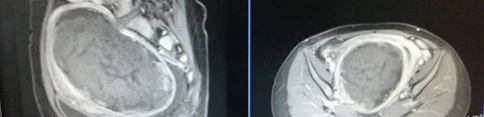

(子宮肌瘤12cm,海扶刀®設(shè)備治療總用時70分鐘)